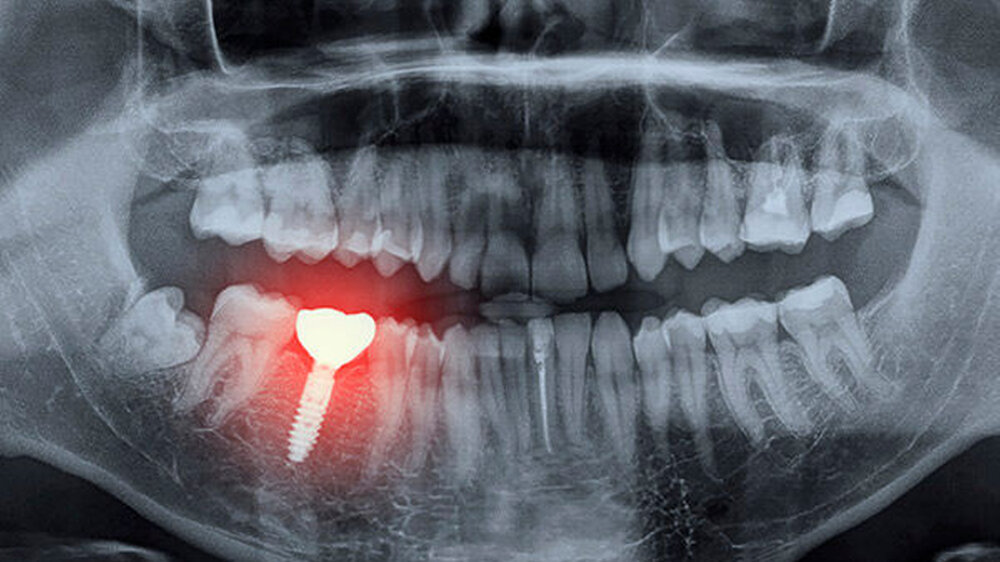

Während des Untersuchungszeitraums erhielten 5.456 Patienten ihr erstes Implantat (Durchschnittsalter 53 Jahre). Die mediane Follow-up-Dauer betrug 5,3 Jahre (Interquartilbereich: 2,3 bis 10,2 Jahre). Bei 4.927 Patienten kam es nicht zu einem Implantatversagen. Dem gegenüber ermittelten die WissenschaftlerInnen 529 Patienten mit Implantatversagen.

In der Gruppe der Patienten mit dem SSRI Sertraline in der Vorgeschichte war ein erhöhtes Risiko für Implantatversagen feststellbar. Das Risiko, das Implantat zu verlieren, lag in dieser Population um 60 Prozent höher. Die Einnahme von SSRI zum Zeitpunkt der Implantation oder eine SSRI-Anwendung nach der Implantion waren nicht in signifikantem Maße mit einem erhöhten Risiko für Implantatversagen verbunden.

Diese Ergebnisse deuten darauf hin, dass eine Langzeitmedikation mit SSRI die Knochenheilung während der kritischen Phase der Heilung der Knochenimplantat-Grenzfläche negativ beeinflusst. Weiterin legen die Ergebnisse nahe, dass die Einnahme mehrerer SSRI das Risiko eines Implantatversagens signifikant erhöht. Im Vergleich zu Patienten ohne SSRI-Anamnese hatten jene, die zwei oder mehr SSRI verwendeten, ein signifikant höheres Risiko das Implantat zu verlieren.